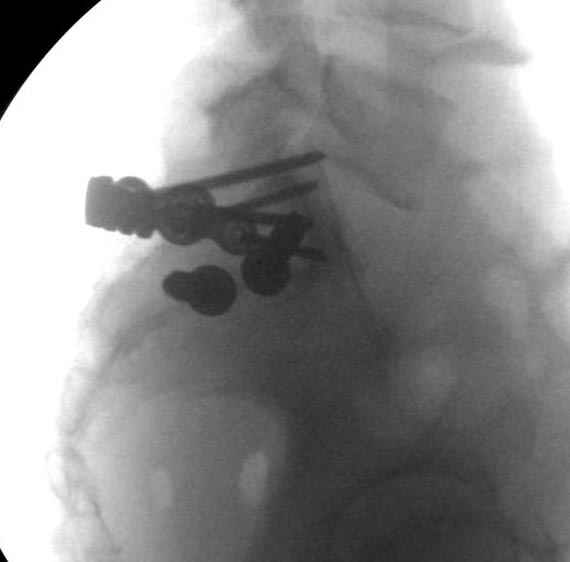

Здесь слайды случая больного с политравмой, включающей сегментарный перелом бедра и повреждение таза с нарушением тазового кольца, разрыв симфиза и перелома крестца зон 2 и 3.

На множественных слайдах важные моменты операции. Хотел бы подчеркнуть, как важно иметь возможности всех необходимых ренгенограмм, включая компютерную томографию и стандартных внутритазовых рентгенограмм (инлет и оутлет).

Djoldas Kuldjanov, MD

Department of Orthopedic Surgery

St. Louis University Medical Center